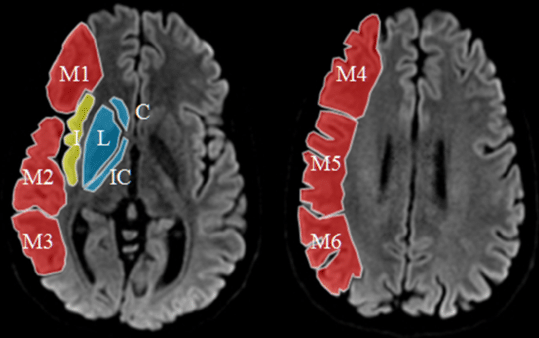

Score ASPECT

Le score ASPECT (Alberta Stroke Program Early CT Score) est un outil de quantification précoce de l’ischémie cérébrale. Le score est établi sur les lésions ischémiques détectées au scanner sans injection, un score à 10 étant normal et à 0 avec une ischémie totale dans la zone étudiée.

Le score est établi à partir de deux plans de coupes scanographiques axiaux standard :

• le premier passant par le thalamus et les noyaux lenticulaires ;

• le deuxième passant par les ventricules latéraux et adjacents au bord supérieur des ganglions de la base, de telle sorte que ceux-ci ne sont pas vus.

Entre ces deux plans de coupe, le territoire de l’artère cérébrale moyenne est divisé en 10 régions, chacune valant un point :

• 3 points sont attribués pour les structures sous-corticales ;

• 7 pour les parties corticales.

Un point est soustrait pour chaque région où l’on note un changement ischémique précoce :

• un score ASPECTS de 10 signifie un scanner normal ;

• un score ASPECTS de 0 signifie une ischémie diffuse à tout le territoire de l’ACM.

L’utilisation d’ASPECT est limitée au territoire de l’ACM. De ce fait, l’on ne peut pas y recourir pour l’infarctus de l’artère cérébrale antérieure ou vertébro-basilaire.